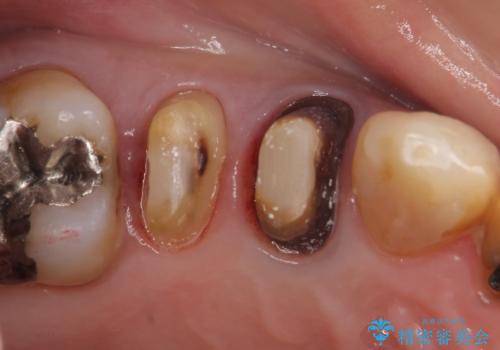

- 右上4番目の歯が黒くなっているのが気になるといらっしゃった方の症例です。

再根管治療後、オールセラミッククラウンによる補綴を行いました。

右上5も虫歯があったためオールセラミッククラウンによる補綴を行っております。